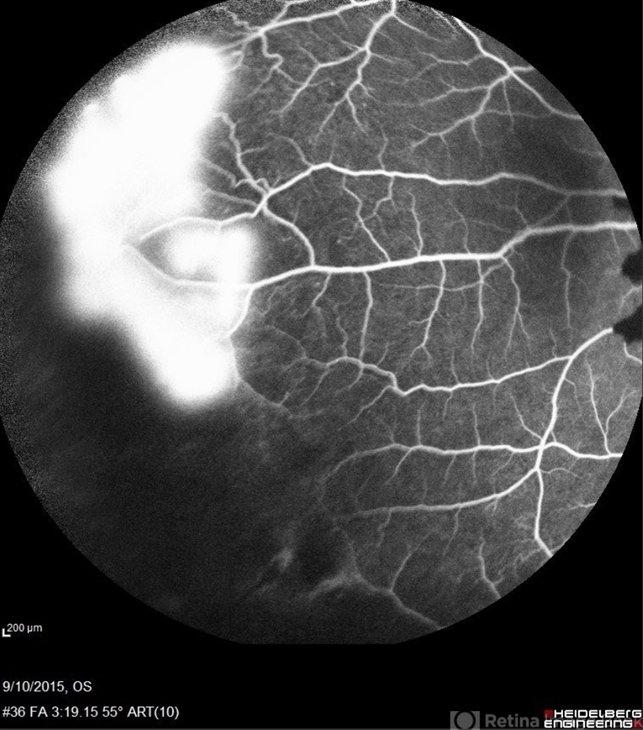

sickle cell retinopathy, peripheral retinal neovascularization, sea fan

Scanning laser ophthalmoscope

Angiography showed normal vessels posteriorly but severe capillary drop out throughout the periphery OU with scattered severe neovascularization at the edge of the capillary drop out peripherally.